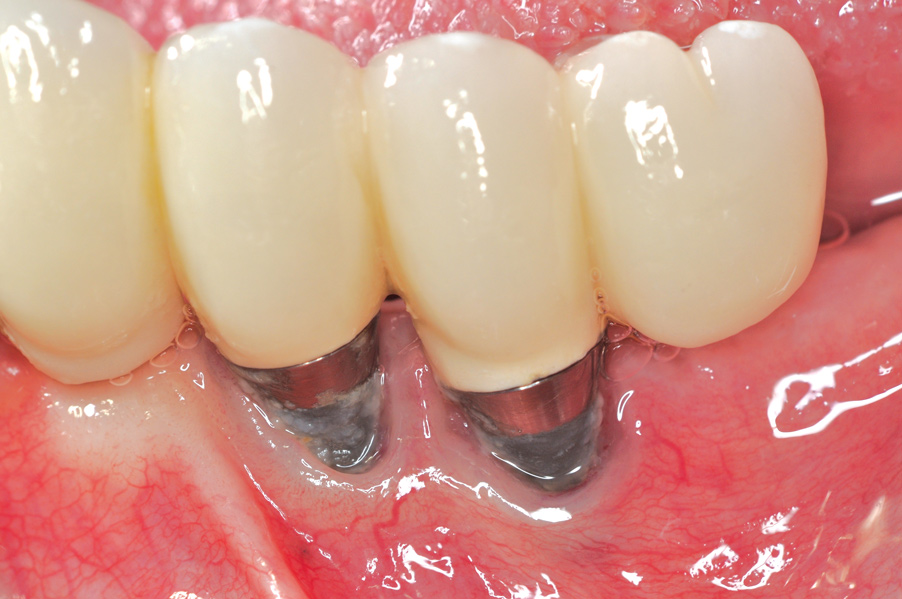

Fig 4. Clinical view of the area 3 months post-therapy. Shallow probings of 3 mm were present around the dental implants with absence of bleeding. However, the mucogingival deformities remained on the premolar implants and would require treatment.

Figure 4